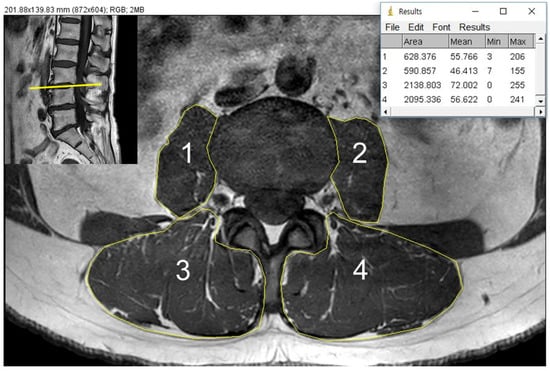

2.3. CSA and Fat Infiltration Measurements